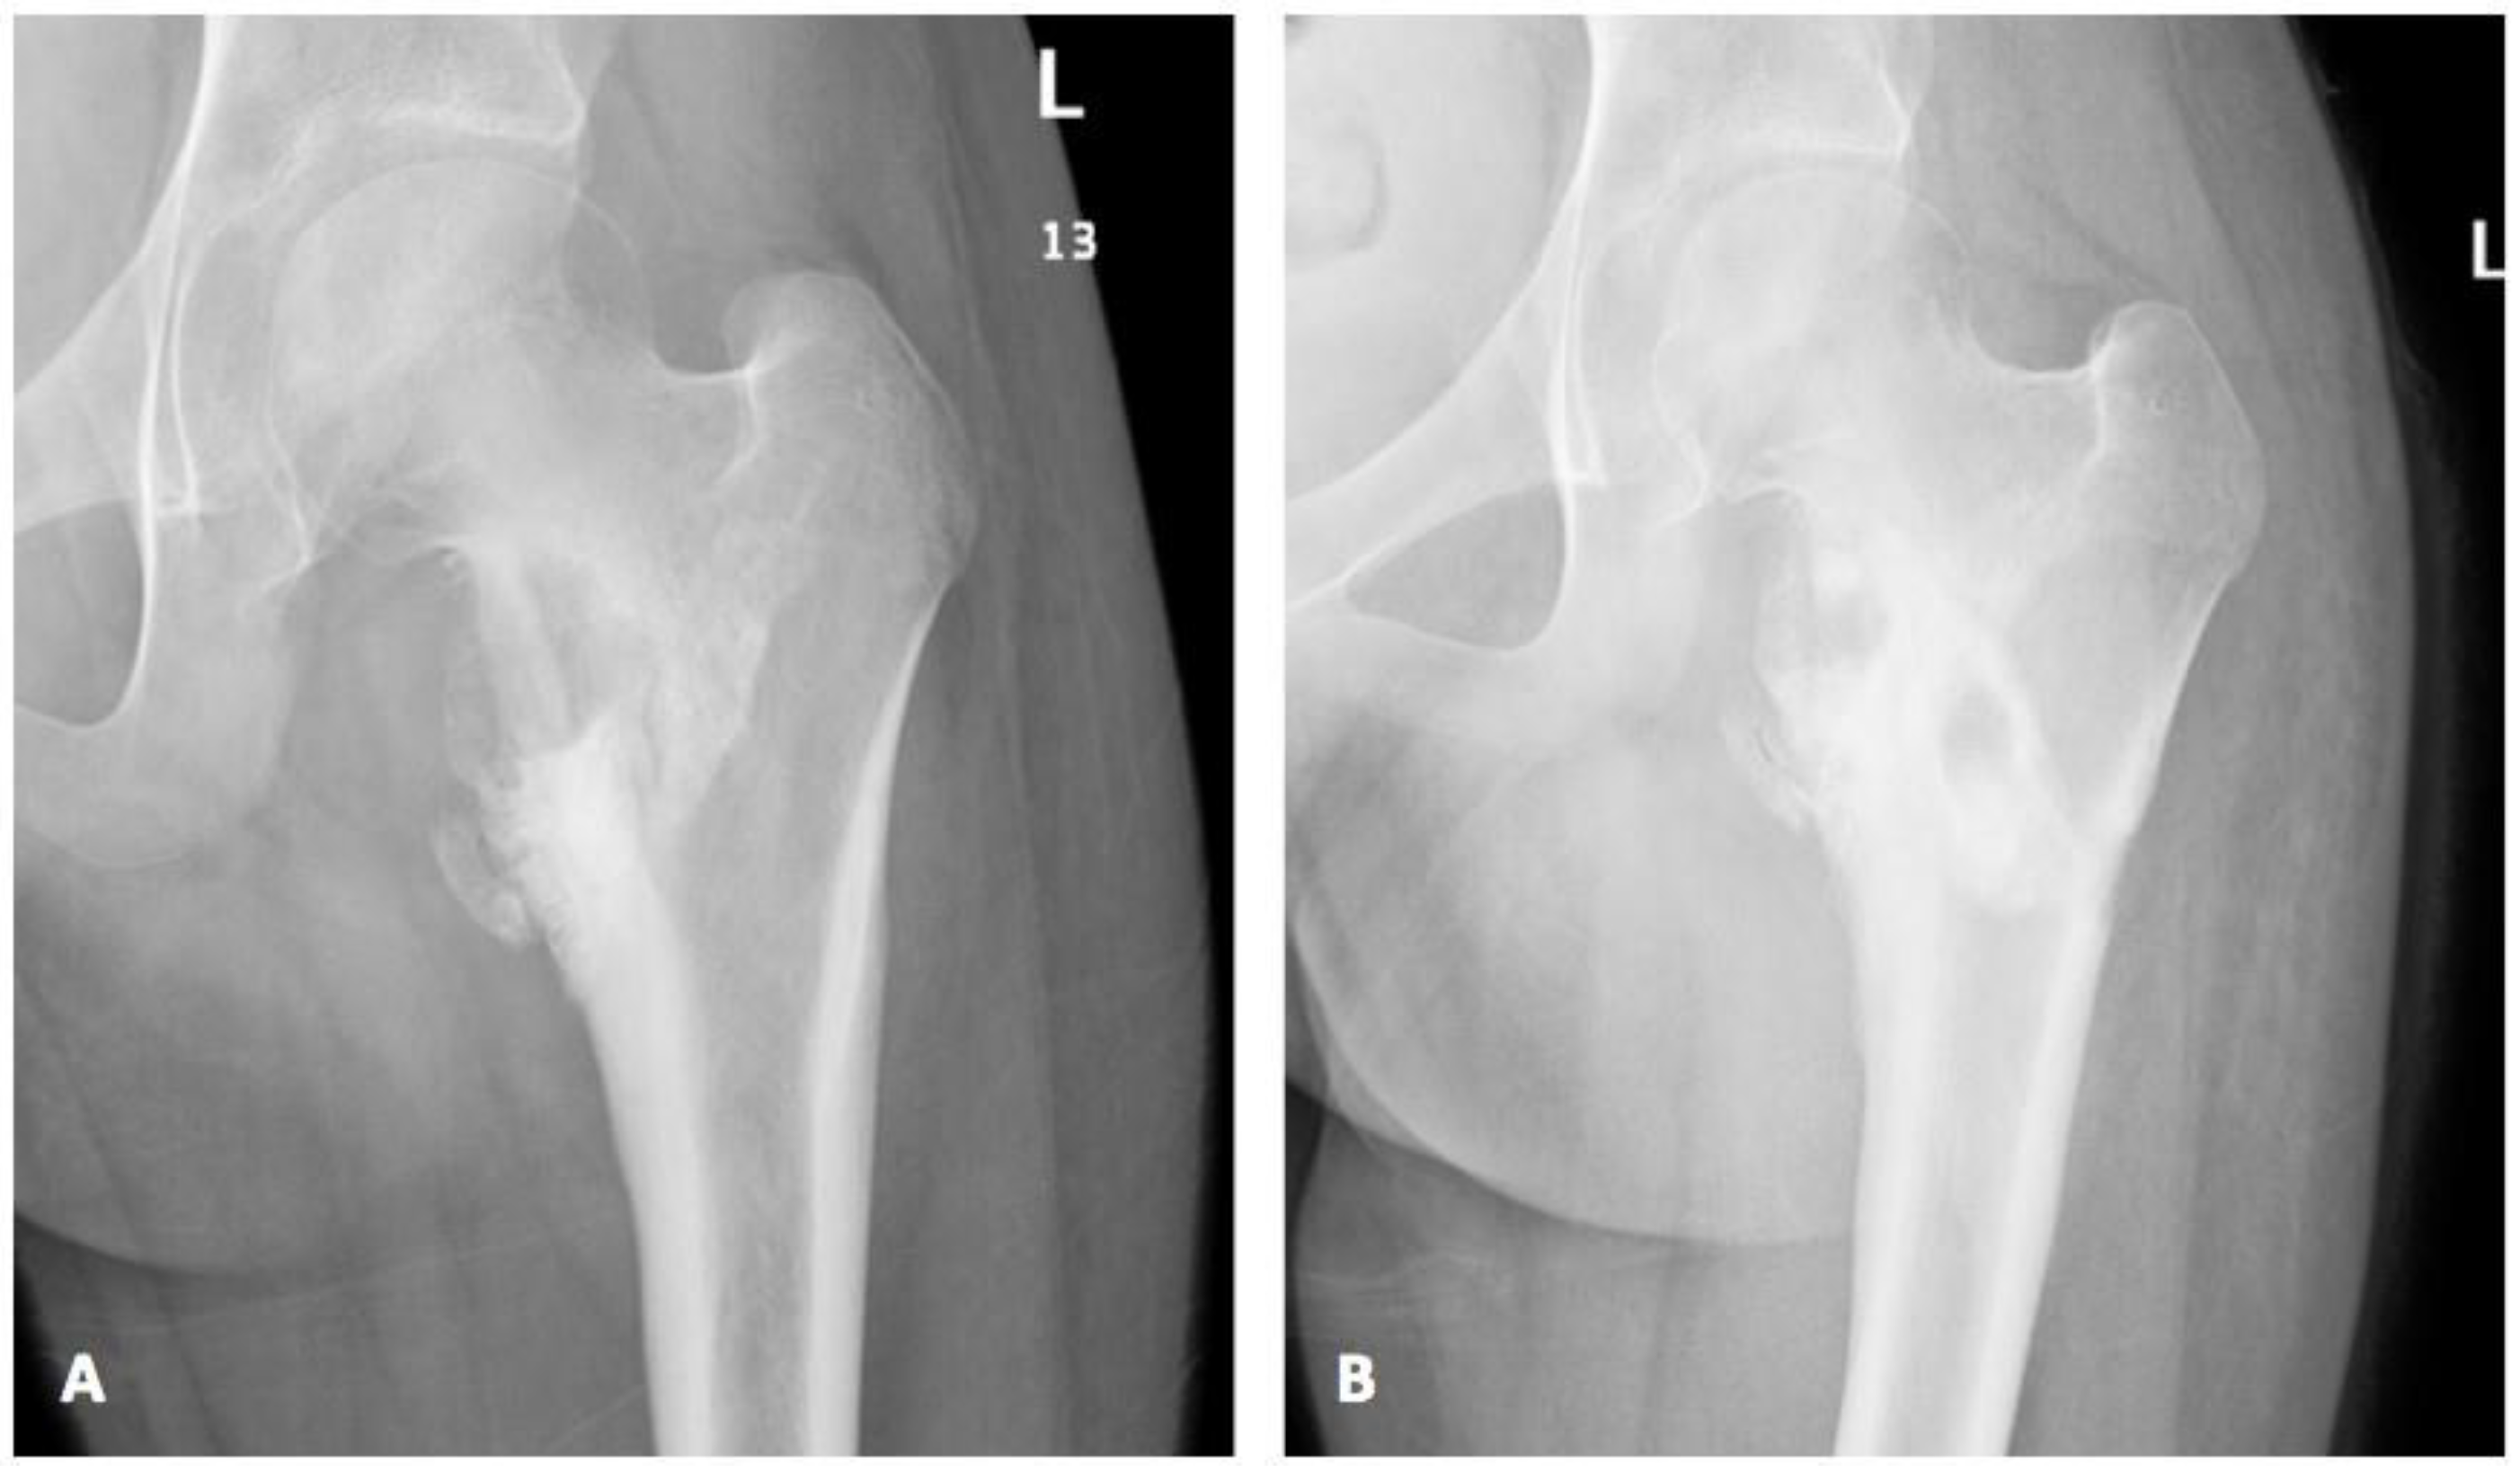

2. Case

| Index case | 12Y/F | Healthy child | Chronic osteomyelitis | Tissue culture | P. species | VRC total 6 months with surgical debridement | Resolution |